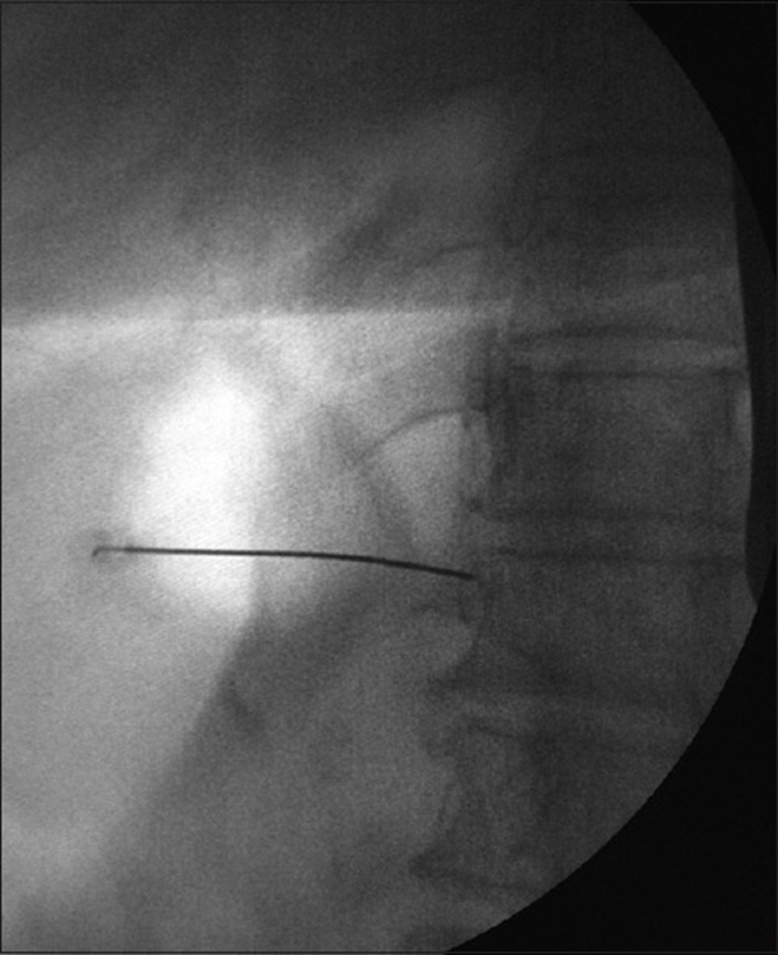

A 20 or 22G, 15 cm needle is inserted paravertebrally, using a tunnel view, in the direction of the concave mid-portion of the vertebral body. Try to make contact with the vertebral body. Under lateral fluoroscopy, the needle is advanced to the anterolateral aspect of the T11 vertebral body at the junction of anterior 1/3rd and Posterior 2/3rd in the lateral view. Radiographic imaging should show the tip of the needle just within the contour of the T11 body in an anteroposterior view and at the junction of anterior 1/3rd and Posterior 2/3rd in the lateral view.

The anteroposterior view of the needle position in the splanchnic nerve block

The lateral view of the needle position in the splanchnic nerve block